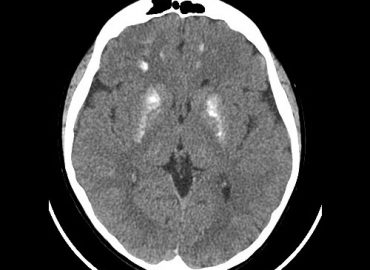

MASCULINO 19 AÑOS APP: NIEGA. ATX: NIEGA. AHF: NIEGA MH: NIEGA MC: CEFALEA, CONVULSIONES